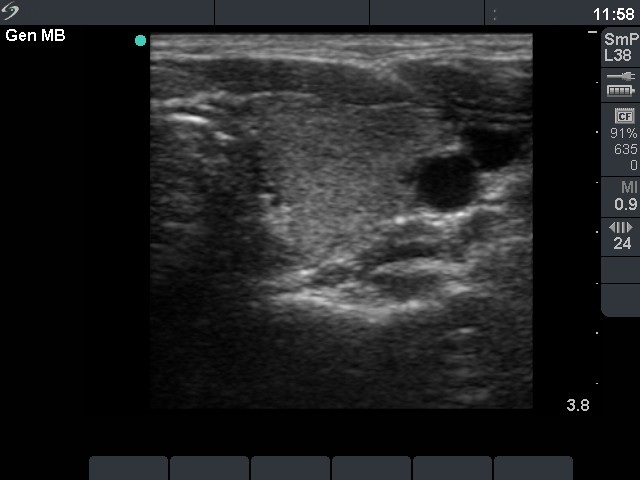

Graves' disease - Case 1049

Follow-up investigation 18 months after first visit (ultrasonographic picture 4)

Patient on daily 5 mg methimazole therapy in euthyroid state

Left lobe, transverse scan. There are minimally-moderately hypoechogenic areas in the otherwise echonormal background.